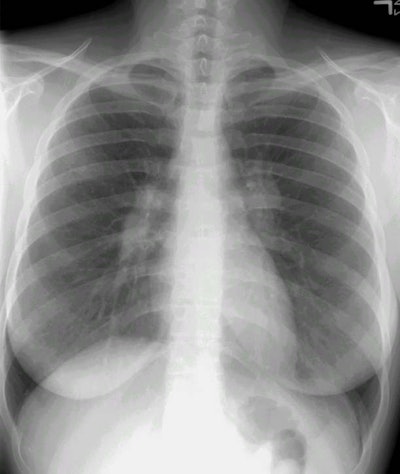

Sarcoid Stage I:

The patient was an asymptomatic active duty troop, who had the chest radiograph performed as a routine screening exam prior to ranger training. The PA chest radiograph demonstrates bilateral hilar fullness (compatible with adenopathy), a slight convexity to the aorto-pulmonary window region (consistent with mediastinal adenopathy), and subtle right paratracheal thickening (also suspicious for adenoapthy). (Click here if you would like to view the lateral exam).

A transbronchial biopsy confirmed the diagnosis of sarcoid. At our institution, asymptomatic patients do not undergo CT scanning. The patients are followed in pulmonary clinic with serial chest radiograph evaluation.